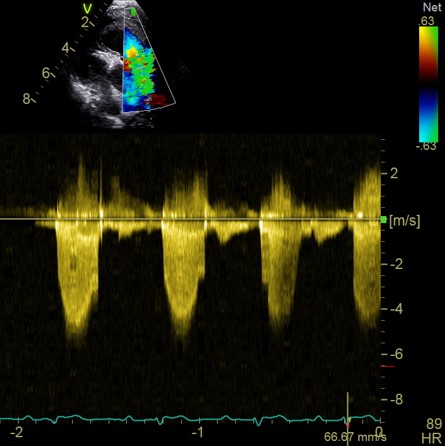

Chaque participant présente un cas clinique (ou plusieurs images) pour revoir le protocole d'échocardiographie et échanger :

Le formateur proposera également quelques coupes échocardiographique non conventionnelles et quelques cas “pièges” pour approfondir l'analyse et la réflexion.